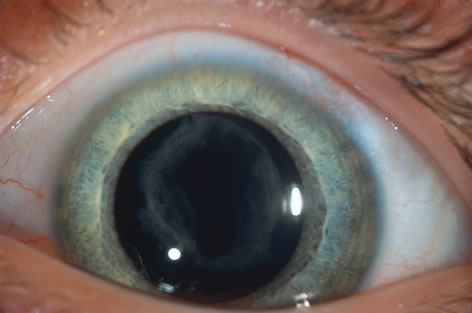

When phacoemulsification became available, it was quickly applied to the removal of children's cataracts because it provided the surgeon with better control of the flow of irrigating solutions and provided improved control of the aspiration flow and pressure.4 The instrument also added a new capability, that of being able to mechanically disrupt the lens nucleus and cortex to facilitate aspiration of the lens. Although the phacoemulsification instrument was helpful for removing lens cortex, it was ineffective in cutting or removing the posterior lens capsule. At the conclusion of the phacoemulsification procedure, the posterior capsule was left intact. When capsular opacification occurred, it was treated with a discission procedure, an operation that consisted of making a cut in the posterior capsule with a bent needle, a Ziegler knife, or a modification of the latter (Fig. 1). If the membrane was thick and resisted opening with a knife, an intraocular scissors was necessary to open the lens capsule.

The advantage of leaving the posterior capsule of the lens intact after cataract surgery is that it retains a barrier between the anterior chamber and vitreous. This prevents the vitreous from entering the anterior chamber, and it theoretically preserves the ocular anatomic relationships after cataract surgery. The disadvantage of leaving the posterior lens capsule intact is that when the capsule opacifies, a second procedure is needed to re-establish a clear visual axis. To achieve this, a second anesthetic is administered and an incision is made into the clear cornea. The chamber is deepened with a viscoelastic material and a knife or other instruments are introduced into the anterior chamber to cut or tear the posterior capsule so that the visual axis can be cleared (Fig. 1).